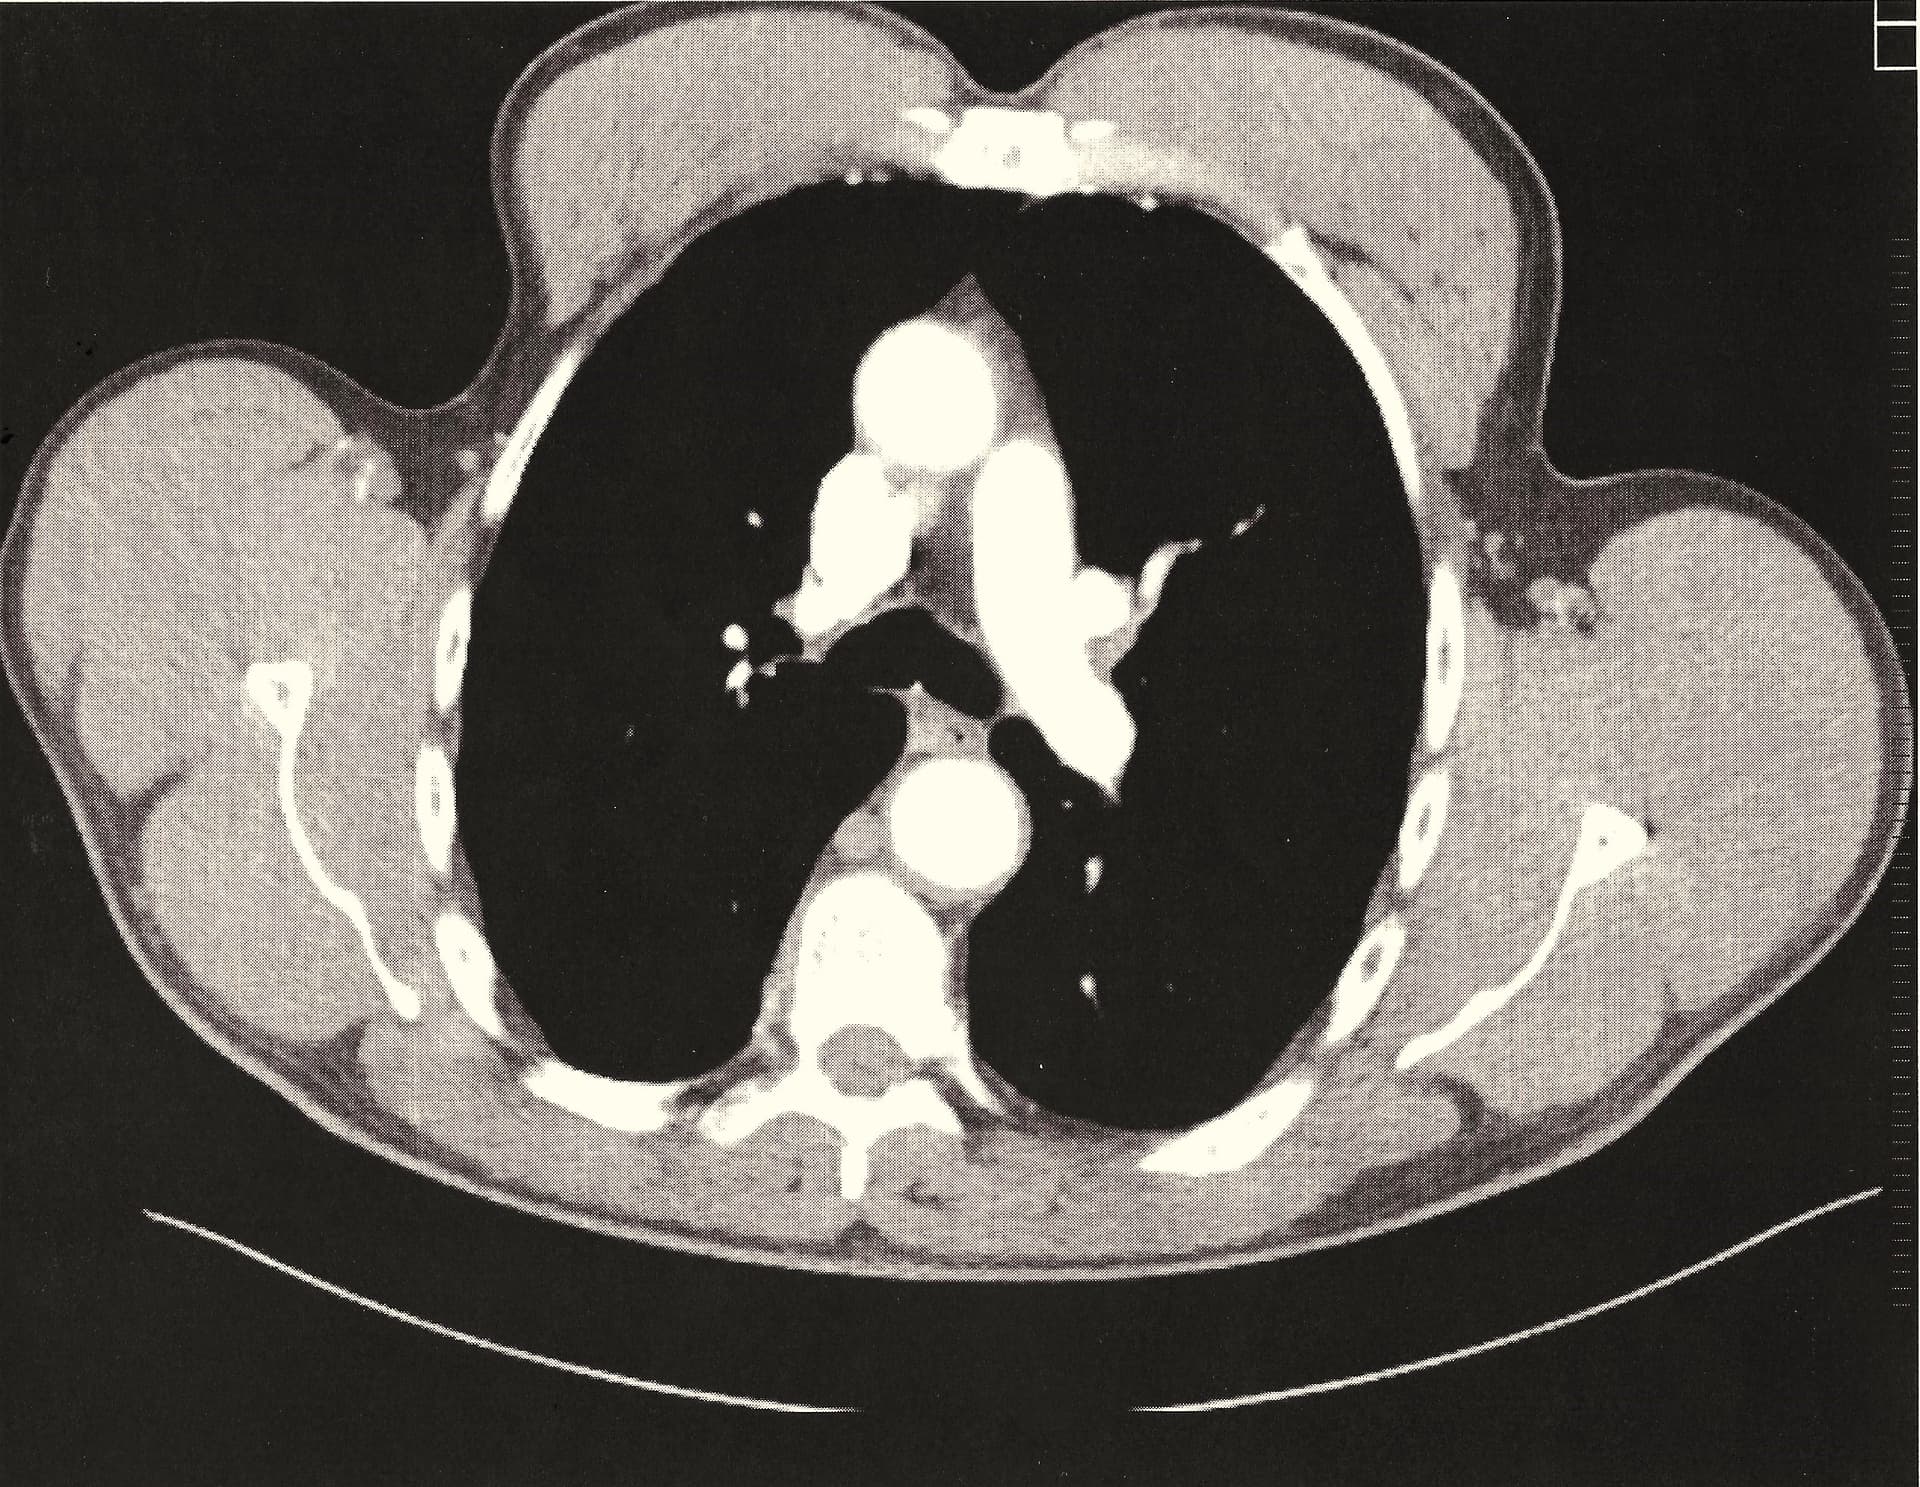

And now my thymus at the top - pic 25/67 and one layer down - cutting through it… pic 26/67 - it is big, full and fat free.

So there you are… now only using small HGH dose of 2 iu for maintenance every other day, a bit more when I feel skin damage or other body trauma needs a kick. Next to rapamycin – HGH is the best addition to my healthspan plan followed by TRT. In this order, Rapa, HGH, and TRT. I think all three are rocking me.